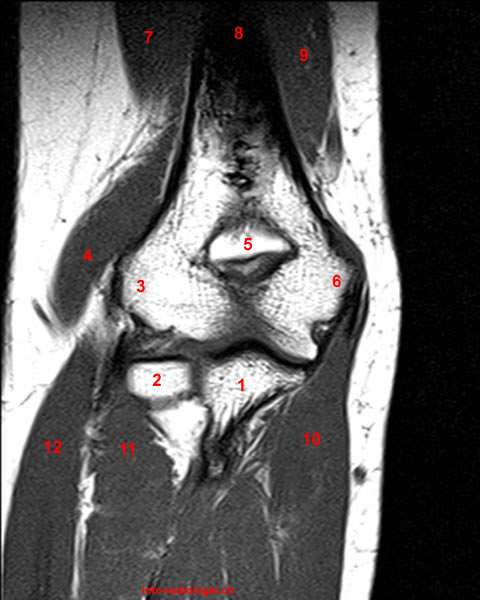

1, Ulna. 2, Radial head. 3, Lateral epicondyle. 4, Extensor carpi radialis longus muscle. 5, Olecranon fossa. 6, Medial epicondyle. 6a, Common flexor tendon. 7, Triceps muscle (lateral head). 8, Humerus. 9, Triceps muscle (Medial head). 10, Flexor digitorum superficialis muscle. 11, Supinator muscle. 12, Extensor digitorum muscle.